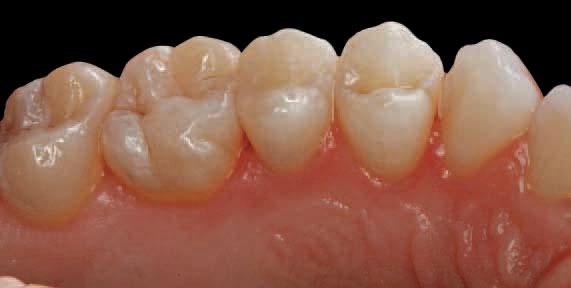

Final finishing and polishing were completed using appropriate finishers. A series of

Astropol finishing and polishing points (Ivoclar Vivadent) were used to complete the restoration. Gray finishing points were used to smooth the surface (Fig. 11).

Green polishing points were used to polish the surface (Fig. 12). Pink polishing points were used to achieve a high gloss (Fig. 13). Because the optical properties of this material are designed specifically to match the refractive index of the fillers and polymer matrix, the restoration appeared imperceptible from the surrounding tooth structure because of the enamel-like translucency of 15%.